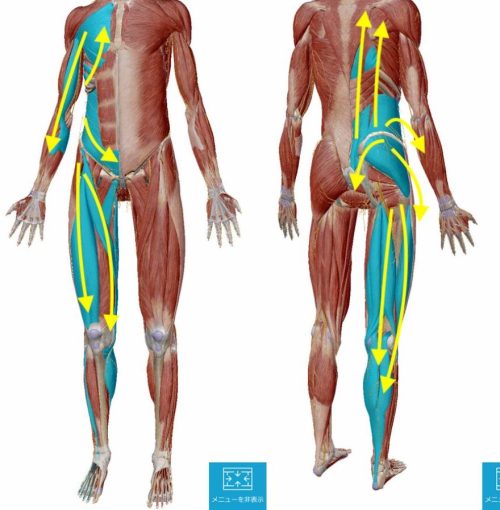

身体全体にの連携を考えた施術でヘルニアは治る!

ヘルニアの部分や痛い場所に囚われず、身体全体の連携を考えて関節と神経ルートを調整し身体全体の連携を取り戻せば殆どの場合に痛みは消えます。

下の図のように腰の筋肉は骨盤だけでなく足や背中、腕にも繋がっています。その為、腰だけを診る治療法や骨盤の歪みだけを診る治療法や筋膜、骨格などを主に診る治療法では見落としてしまう部分があり、それがヘルニアの腰痛がなかなか治らない原因の1つにもなっています。

毎日のお仕事や家事などで披露が蓄積すると筋肉は硬直し縮んで黄色い矢印の方へ引っ張る力が生まれます。腰を中心に上にも下にも引っ張られることで、骨盤に歪みが生まれたり腰椎を圧迫してヘルニアになったりします。

ヘルニアで腰が痛いからと腰だけ診ていては治らないのです。

この図のように腰に連携している筋肉は多数あり、それらの筋肉が硬直して縮むことにより筋肉の末端が付着している骨盤などの位置にズレが生じ痛みを生み出しているのです。

例えばこの図のように背中や肩が張っていて動きが悪い状態の時に太ももが硬直して縮んだ場合には下方に引きずり込まれる形になり筋肉のズレが生じて骨盤までが歪んで腰に痛みがでます。

例えば肩こりや首コリが酷い場合に、長時間座っていたり、中腰や屈伸などの脚への負担が大きい場合には、この図のように上下に縮んだ筋肉が引っ張り合うので中間部分の腰に痛みが生じます。

例えMRIでヘルニアと診断があっても、それが痛みの直接の原因ではないということです。